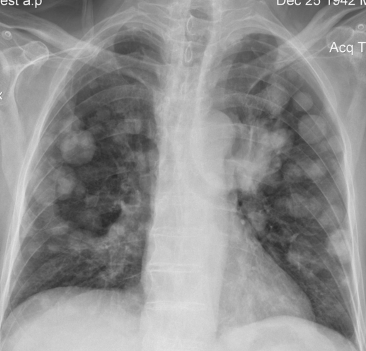

Rx toracică, incidență P-A

DESCRIERE:

pe tot teritoriul pulmonar, bilateral → opacități nodulare multiple de dimensiuni variabile, intensitate medie-mare, omogene, cu contur net

distribuție anarhică

blocuri adenopatice la niv. hilurilor pulmonare

DX: MTS pulmonare hematogene

DD:

hidatidoză - dimensiuni mai mari

bronhopneumonie - contur neregulat, neomogene, distribuție bazală